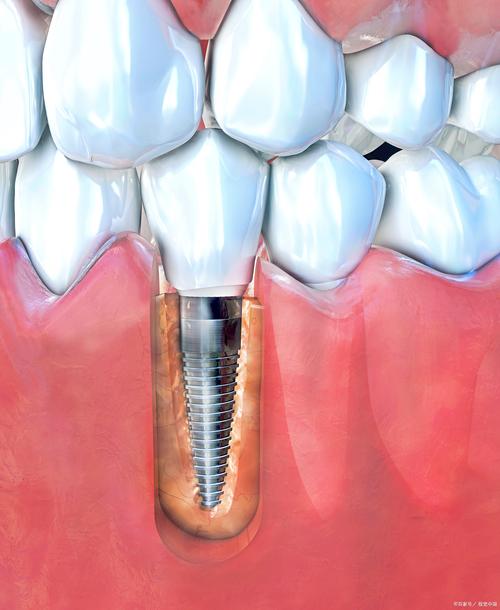

牙槽骨的宽度是种植牙成功的核心基础,如同高楼需稳固地基,若宽度不足,会导致种植体植入后初期稳定性差,甚至无法植入,直接影响种植牙的长期使用效果和安全性,临床上,不少患者因缺牙后骨吸收、牙周病或先天发育问题,面临牙槽骨宽度不足的困扰,但这并非种牙的“终点”,通过现代口腔技术可有效解决。

牙槽骨宽度不足主要由以下因素导致:缺牙后,牙槽骨失去咀嚼刺激,逐渐发生废用性萎缩,尤其后牙区骨宽度吸收更明显;牙周病导致牙槽骨破坏,骨量减少;部分患者先天牙槽骨发育较窄;长期佩戴不合适的活动假牙,压迫牙槽骨,加速吸收,这些情况会导致种植体植入空间不足,若强行植入,可能引发骨壁穿孔、邻牙损伤,或因骨支持量不足,后期出现种植体松动、折断,甚至种植体周围炎。